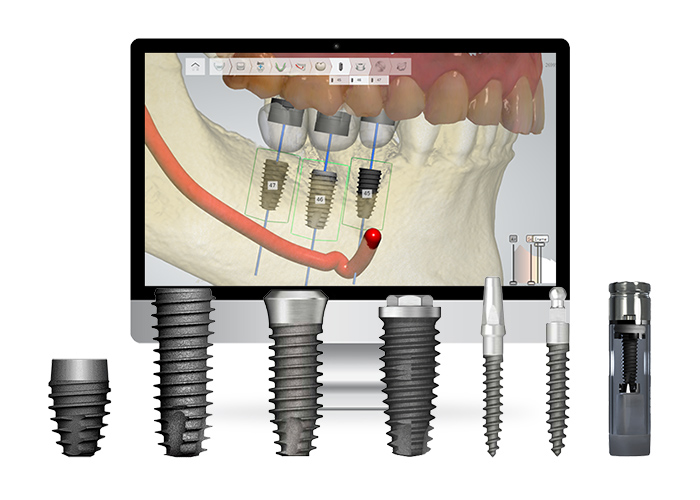

서울대병원 보철과 전문의가 직접 시술 전 3D 진단 계획 수립하여

더 정확하고 안전한 임플란트 시술이 가능합니다.

연세꿈꾸는치과에서는 치료 과정을 디지털 데이터를 통해 진행하여 실제 수술 전 3D 컴퓨터로 모의수술을 미리 보고 치료를 계획합니다.

고난이도 임플란트, 무절개 임플란트, 내비게이션 임플란트, 맞춤형 임플란트, 임플란트 재수술 등

풍부한 경험과 노하우로 3D 정밀진단 맞춤 솔루션을 제공합니다.